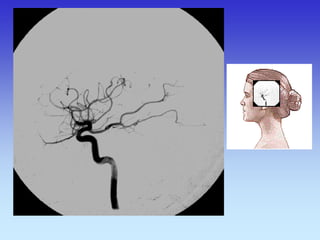

METODE PRIKAZA KRVNIH ŽILA

•UZ-DOPPLER

•DSA

•CTA

•MRA

B-mod i obojeni Doppler karotidne arterije

VASKULARNA OPSKRBA WILLIS-ijev prsten

a. cerebri ant.

a. cerebri media

a. cerebri post.

VASKULARNA OPSKRBNA PODRUČJA